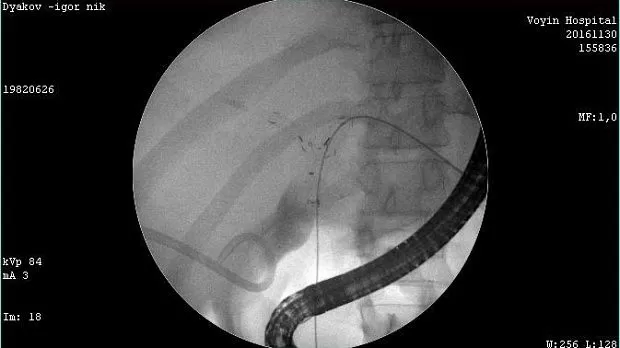

Молодой человек 33 г. Диагноз подтвержден. Стентирован пластиковыми стентами, потом самораскрывающимися. Одномоментно анте и ретроградно - с хорошим результатом. Дальше был поставлен в очередь на трансплантацию. Дальнейшая судьба не известна.